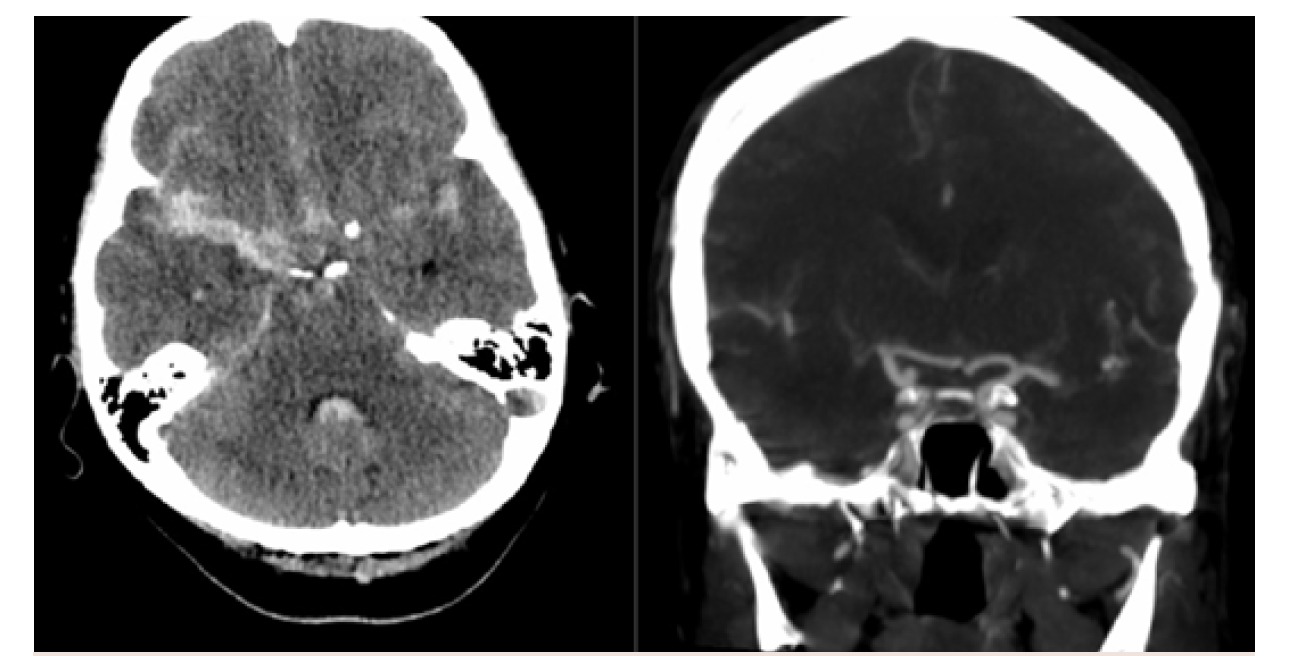

In the first case, a healthy 59-year-old patient presented to the ER with aneurysmal subarachnoid hemorrhage and an unusual ruptured right internal carotid artery dorsal wall aneurysm (Figure 6). While each practice approaches these somewhat differently, this is a flow diversion case for Goodman Campbell Brain and Spine.

Access in a case such as this must be obtained with extreme care and the utmost precision. Note the clarity and visualization of the support catheter (0.058" Navien [Medtronic]) and microcatheter (Phenom 27 [Medtronic]), even without the presence of a wire (Figure 7).